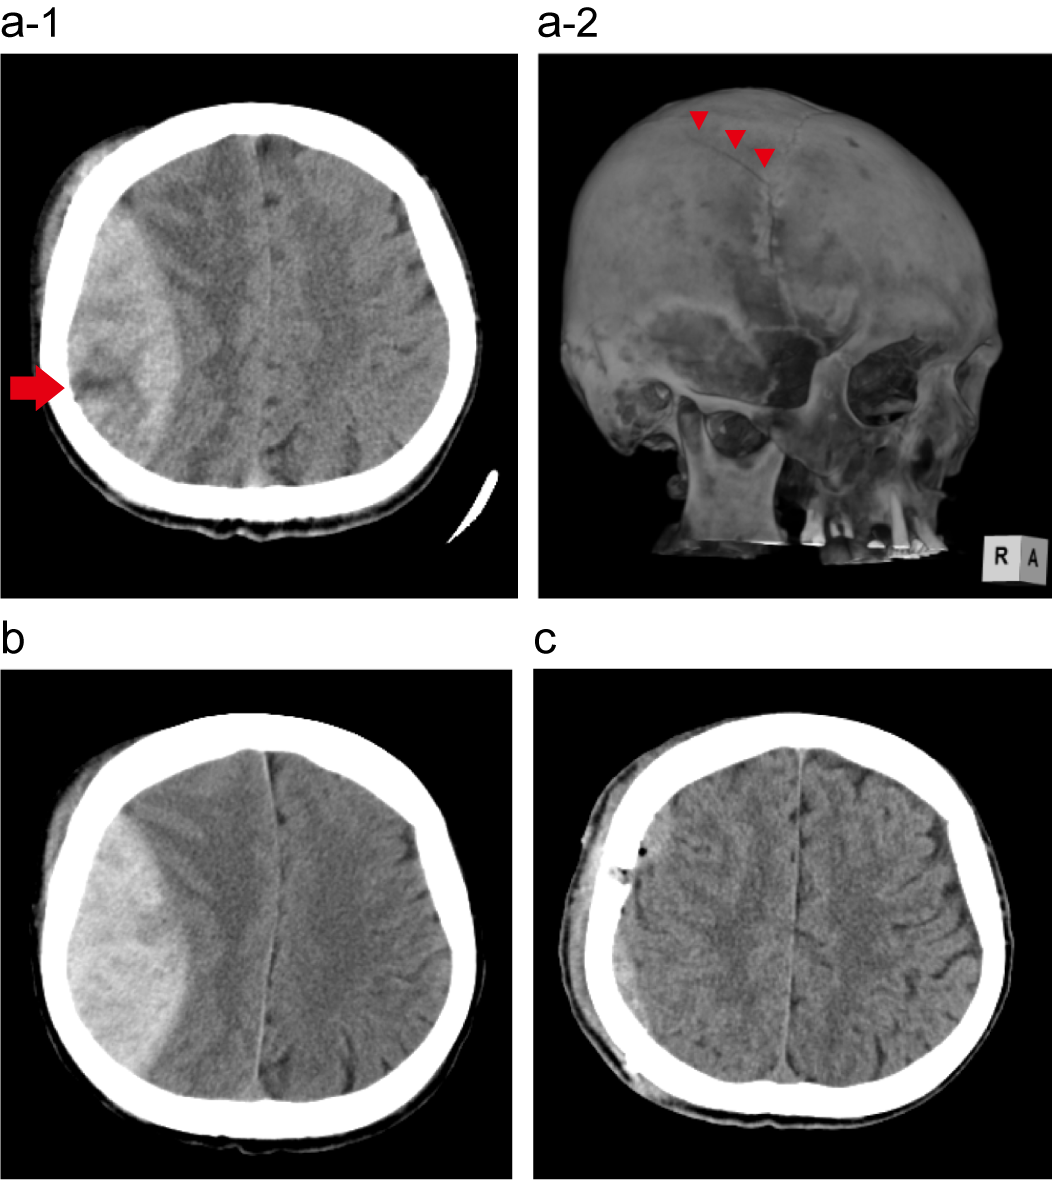

急性硬膜外血腫、みぎ頭頂骨骨折の症例

50歳代、男性。飲酒後に階段6段程度を転落し、右側頭部打撲し前医から救急搬送された。

a. 受傷直後の頭部CT。みぎ側頭-頭頂部に内部一部低吸収値を伴う(a-1:矢印、swirl sign)急性硬膜外血腫、みぎ頭頂骨骨折(a-2:3D再構成画像、矢頭)を認め、当院へ転送された。

b. 転送後の頭部CT。来院時は酩酊状態で意識障害の評価は困難であったが、軽度ひだり片麻痺および血腫の増大を認め、緊急手術後に入院となった。術所見で中硬膜動脈からの出血を認めたため、十分に止血処理を行い、脳腫脹は認めなかったため型通りに閉頭した。

c. 術後1週間の頭部CT。合併脳損傷なども認めず、術後10日で独歩退院となった。